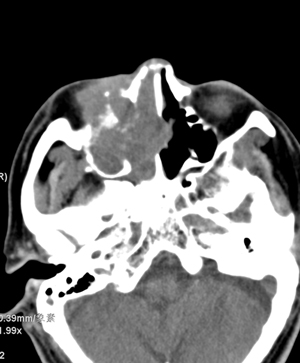

以下是引用影象小辈在2008-5-4 13:34:00的发言:[br]鼻腔及右侧上颌窦 筛窦内软组织密度影, 相邻鼻中隔、鼻甲及窦壁骨质破坏吸收,病灶延伸至鼻咽腔及右侧眼眶 多考虑为1.乳头状瘤 2.息肉 建议增强及活检

以下是引用peijunlong在2008-5-4 13:35:00的发言:[br]考虑右侧鼻腔内翻性乳头状瘤[br]好发:中老年人。[br]ct:1:一侧鼻腔内肿块经扩大的自然孔道长入鼻窦,是其顺自然孔道蔓延的特点[br] 2:鼻腔,鼻窦扩大,窦壁压迫性骨质破坏。[br] 3:广泛生长的肿瘤可侵犯邻近结构,如眼眶、翼腭窝和颅内。

以下是引用不学无术在2008-5-4 20:43:00的发言:[br]病人已在齐鲁医院穿刺活检病理结果:中分化鳞癌。